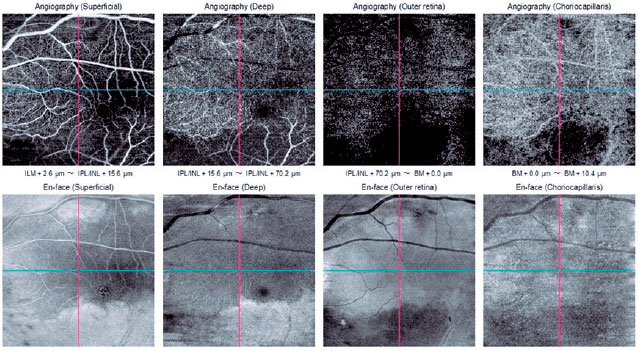

OCT-A of the right eye showed signs of normal flow and vascularization in all slabs. OCT-A of the left eye showed signs of a decrease in the superficial retinal plexus slab, except in a well-delimited band of the macular area that extended from the optic disc to the temporal macula. The same decreased blood flow was found in the deep retinal plexus slab and in the outer retinal slab. Signs of decreased flow in the choroidal slab were also found (Figure 3).

Figure 3. OCT-A of the left eye with the decreased flow sign in the superficial retinal plexus, deep retinal plexus, outer retina, and choroidal slab, with the exception of a well-delimited band of the macular area that extends from the optic disc to the temporal macula.